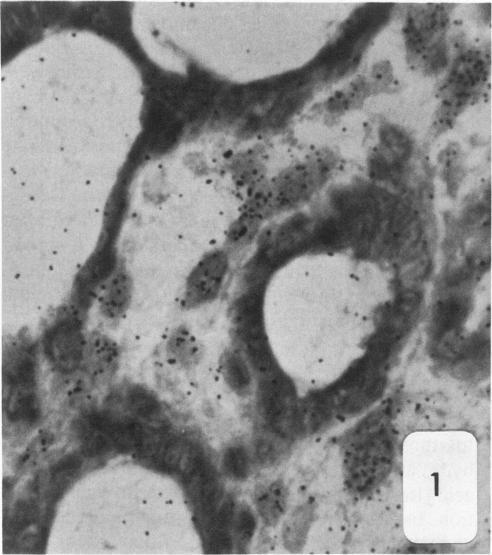

Dunning R3327-H rat prostate adenocarcinoma cells, when grown in syngeneic (Copenhagen) rats or nude mice, produce tumors with prominent hypercellular stroma. The authors have previously demonstrated the presence of anomalous steroid-sensitive cells in both the epithelium and stromal compartments of this model system. In order to better understand the histogenesis of these cells, the authors studied samples of the tumor which were radiolabeled overnight with tritiated dihydrotestosterone (3H-DHT). Frozen sections of the tissues were thaw-mounted onto autoradiographic emulsion-coated slides to permit silver grain identification in association with nuclei of androgen-sensitive cells. Surprisingly, numerous silver grains were found to be associated with nuclei of large cells within the stroma. Therefore, these cells were termed "epithelioid" pending confirmation of their origin. To further define these cells and their relationship to the surrounding matrix, autoradiograms have now been examined immunohistochemically with antibodies directed against the basement membrane glycoprotein, laminin, as well as antibodies specific for intermediate cytoskeletal filaments. Following identification of acinar basement membranes, epithelioid cells were identifiable both in the stroma and in the acinar epithelial cell layer. Histochemical staining with acid phosphatase, a marker for prostatic epithelium, was performed and shown to be present in acinar epithelial cells as well as in epithelioid cells. Additionally, fluorescence-activated cell sorting was employed to characterize the DNA content of cell types within the H tumor. Epithelioid cells were found to be in highest concentration in an aneuploid peak with a ploidy of approximately 6N. The autoradiographic, immunohistochemical, cytometric, and ultramicroscopic studies suggest that 1) epithelioid cells are epithelial derived stromal cells; 2) these epithelioid cells arise by pathologic division of aneuploid neoplastic precursor cells of approximately 3N ploidy, which are found within the prostatic epithelium; and 3) the resulting 6N cells degrade the basement membrane locally, invade the stroma, and populate it. Here, they can be distinguished from fibroblasts by their size, acid phosphatase activity, and hormone receptor content. Thus, the term "epithelioid" is inappropriate; and these cells should be regarded simply as large neoplastic epithelial (LNE) cells. The presence of this cell type suggests that this tumor subline represents a useful naturally occurring model for the study of the initial stages of neoplastic transformation.

邓宁R3327 - H大鼠前列腺腺癌细胞在同基因(哥本哈根)大鼠或裸鼠体内生长时,会产生具有显著细胞增多性基质的肿瘤。作者此前已证明在该模型系统的上皮和基质区室中均存在异常的类固醇敏感细胞。为了更好地理解这些细胞的组织发生,作者研究了用氚化双氢睾酮(3H - DHT)过夜进行放射性标记的肿瘤样本。将组织的冰冻切片解冻后贴在涂有放射自显影乳剂的载玻片上,以便确定与雄激素敏感细胞核相关的银颗粒。令人惊讶的是,发现大量银颗粒与基质内大细胞的核相关。因此,在确认其起源之前,这些细胞被称为“上皮样细胞”。为了进一步定义这些细胞及其与周围基质的关系,现在已用针对基底膜糖蛋白层粘连蛋白的抗体以及针对中间细胞骨架丝的特异性抗体对放射自显影片进行免疫组织化学检查。在确定腺泡基底膜后,在上皮样细胞的基质和腺泡上皮细胞层中均可识别出上皮样细胞。用酸性磷酸酶进行组织化学染色,酸性磷酸酶是前列腺上皮的标志物,结果显示其存在于腺泡上皮细胞以及上皮样细胞中。此外,采用荧光激活细胞分选技术来表征H肿瘤内细胞类型的DNA含量。发现上皮样细胞在非整倍体峰中浓度最高,其倍性约为6N。放射自显影、免疫组织化学、细胞计量学和超微结构研究表明:1)上皮样细胞是上皮来源的基质细胞;2)这些上皮样细胞由前列腺上皮内约3N倍性的非整倍体肿瘤前体细胞的病理性分裂产生;3)产生的6N细胞局部降解基底膜,侵入基质并在其中聚集。在这里,它们可以通过大小、酸性磷酸酶活性和激素受体含量与成纤维细胞区分开来。因此,“上皮样”这个术语并不恰当;这些细胞应简单地视为大肿瘤上皮(LNE)细胞。这种细胞类型的存在表明该肿瘤亚系是研究肿瘤转化初始阶段的一个有用的自然发生模型。